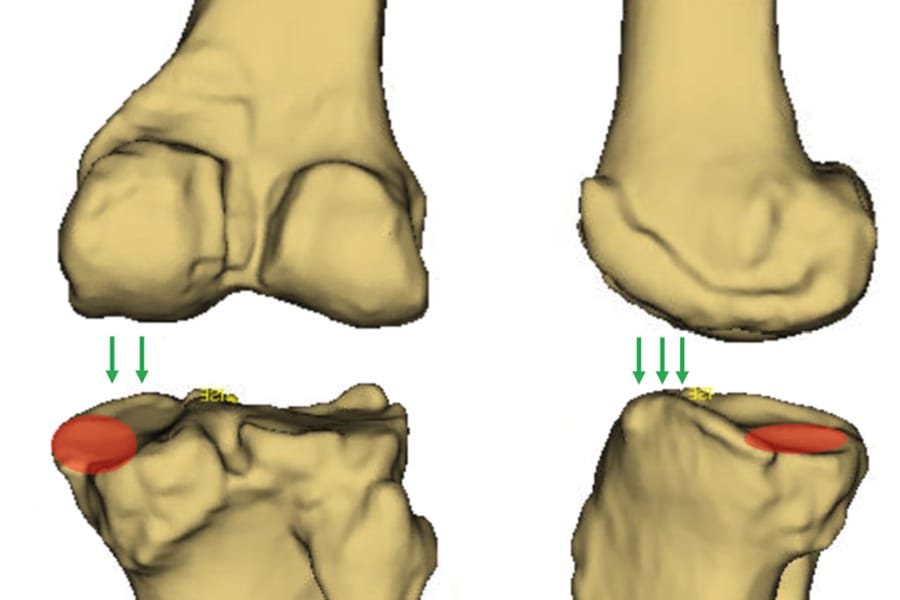

The clinical contributions in this issue address personalized alignment in TKA and examine why individualized TKA facilitates the restoration of native alignment, alongside current concepts and a glimpse into the future of partial knee replacement. A new perspective in cementless total knee arthroplasty broadens the implant discussion, while individualised therapy of femoral neck fractures — the Wiesbaden concept extends the scope to proximal femoral pathology.